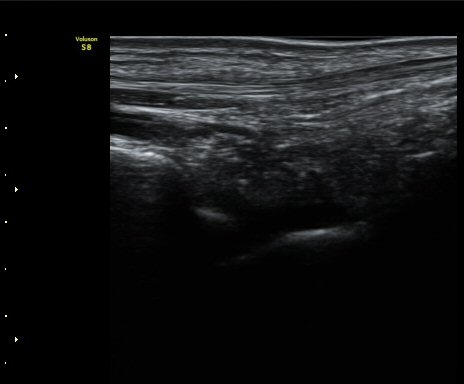

ÃÊÀ½ÆÄÅõ½ÃÇÏ ºÎÇϰ˻翡¼­ ºñ°ñ°ú ÀÎ´ë ºÎÂøºÎ¿Í ºñ°ñ°ú °Å°ñ »çÀ̰¡ ¹ú¾îÁø´Ù

(樨毢 1)

Àü°Å°ñºñ°ñÀÎ´ë ¼Õ»óÀÌ °üÂûµÇ´Â °æ¿ì ¹Ýµå½Ã ÃÊÀ½ÆÄÅõ½ÃÇÏ ºÎÇϰ˻縦 ½ÃÇàÇÏ¿©

ÀδëÀÇ ¿ÏÀü ÆÄ¿­·Î ºÒ¾ÈÁ¤¼ºÀ» º¸ÀÌ´Â °æ¿ì 3ÁÖ ÀÌ»ó ¼®°í°íÁ¤ÀÌ ¹Ù¶÷Á÷ÇÏ´Ù.